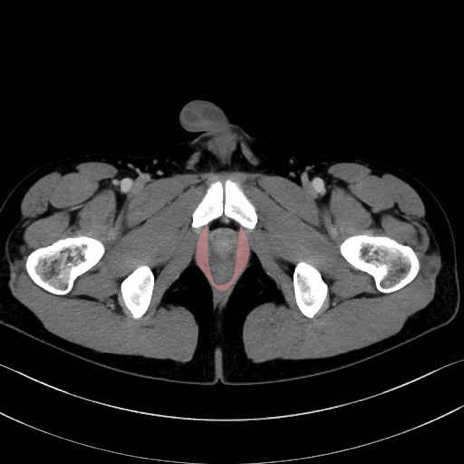

肛門挙筋(levator ani muscle)のCT画像の解剖

肛門挙筋 (Levator ani)